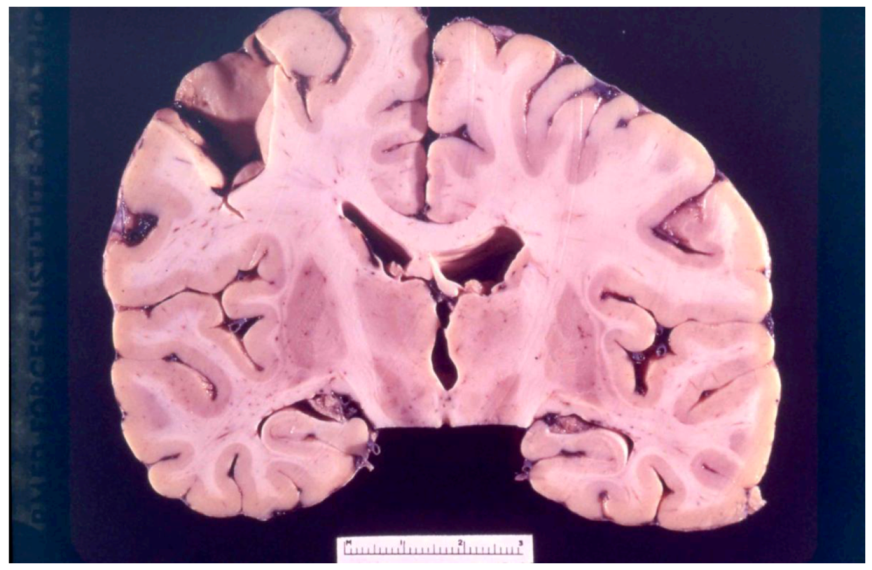

8. Neuropathology

- Klatzo, I.; Gajusek, D.C.; Zigas, V. Evaluation of Pathological Findings in Twelve Cases of Kuru. In Encephalitides; van Boagert, L., Radermecker, J., Hozay, J., Lowenthal, A., Eds.; Elsevier Publ. Comp.: Amsterdam, The Netherlands, 1959; pp. 172–190. [Google Scholar]

- Klatzo, I.; Gajusek, D.C. Pathology of kuru. Lab. Invest. 1959, 8, 799–847. [Google Scholar]

- Fowler, M.; Robertson, E.G. Observations on kuru. III: Pathological features in five cases. Australas Ann. Med. 1959, 8, 16–26. [Google Scholar]

- Neuman, M.A.; Gajdusek, D.C.; Zigas, V. Neuropathologic findings in exotic neurologic disorder among natives of the Highlands of New Guinea. J. Neuropathol. Exp. Neurol. 1964, 23, 486–507. [Google Scholar] [CrossRef]

- Liberski, P.P.; Sikorska, B.; Lindenbaum, S.; Goldfarb, L.G.; McLean, C.; Hainfellner, J.A.; Brown, P. Kuru: Genes, cannibals and neuropathology. J. Neuropathol. Exp. Neurol. 2012, 71, 92–103. [Google Scholar] [CrossRef]

- Hainfellner, J.; Liberski, P.P.; Guiroy, D.C.; Cervénaková, L.; Brown, P.; Gajdusek , D.C.; Budka, H. Pathology and immunohistochemistry of a kuru brain. Brain Pathol. 1997, 7, 547–554. [Google Scholar] [CrossRef]